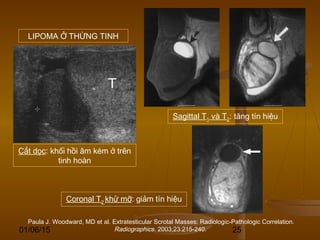

Paula J. Woodward, MD et al. Extratesticular Scrotal Masses: Radiologic-Pathologic Correlation.

Radiographics. 2003;23:215-240.

Cắt dọc: khối hồi âm kém ở trên

tinh hoàn

Sagittal T1 và T2: tăng tín hiệu

Coronal T2 khử mỡ: giảm tín hiệu

LIPOMA Ở THỪNG TINH